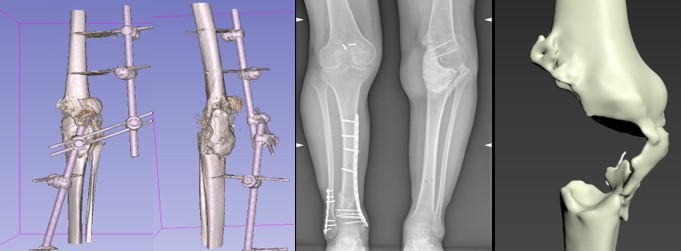

ТЕХНОЛОГІЇ ВІДНОВЛЕННЯ КІСТКОВОЇ ТКАНИНИ У ХВОРИХ З НАСЛІДКАМИ БОЙОВОЇ ТРАВМИ

Пацієнт С,30 років. Військовослужбовець, 01.11.2022 отримав мінно-вибухову травму, вогнепальне уламкове наскрізне поранення нижньої третини правого стегна з відкритим переломом медіального виростка з повним пересіченням підколінної артерії, підколінної вени та підколінного нерва.

Пацієнт Д.,30 років. Військовослужбовець, 15.08.2023 отримав мінно-вибухову травму, вогнепальне уламкове наскрізне поранення нижньої третини правої гомілки.

В лабораторії Біомедичної інженерії ІТО НАМН України виконано проектування індивідуального аугменту.

Пацієнт Д.,30 років.Військовослужбовець, отримав МВТ 25.06.2023 року. На етапах лікування імплантація цементного спейсера правої стегнової кістки з приводу остеомієліту у вересні 2023 року. Інфекційний процес ліквідовано. Госпіталізований на планове хірургічне лікування з метою встановлення протезу типу Hinge.